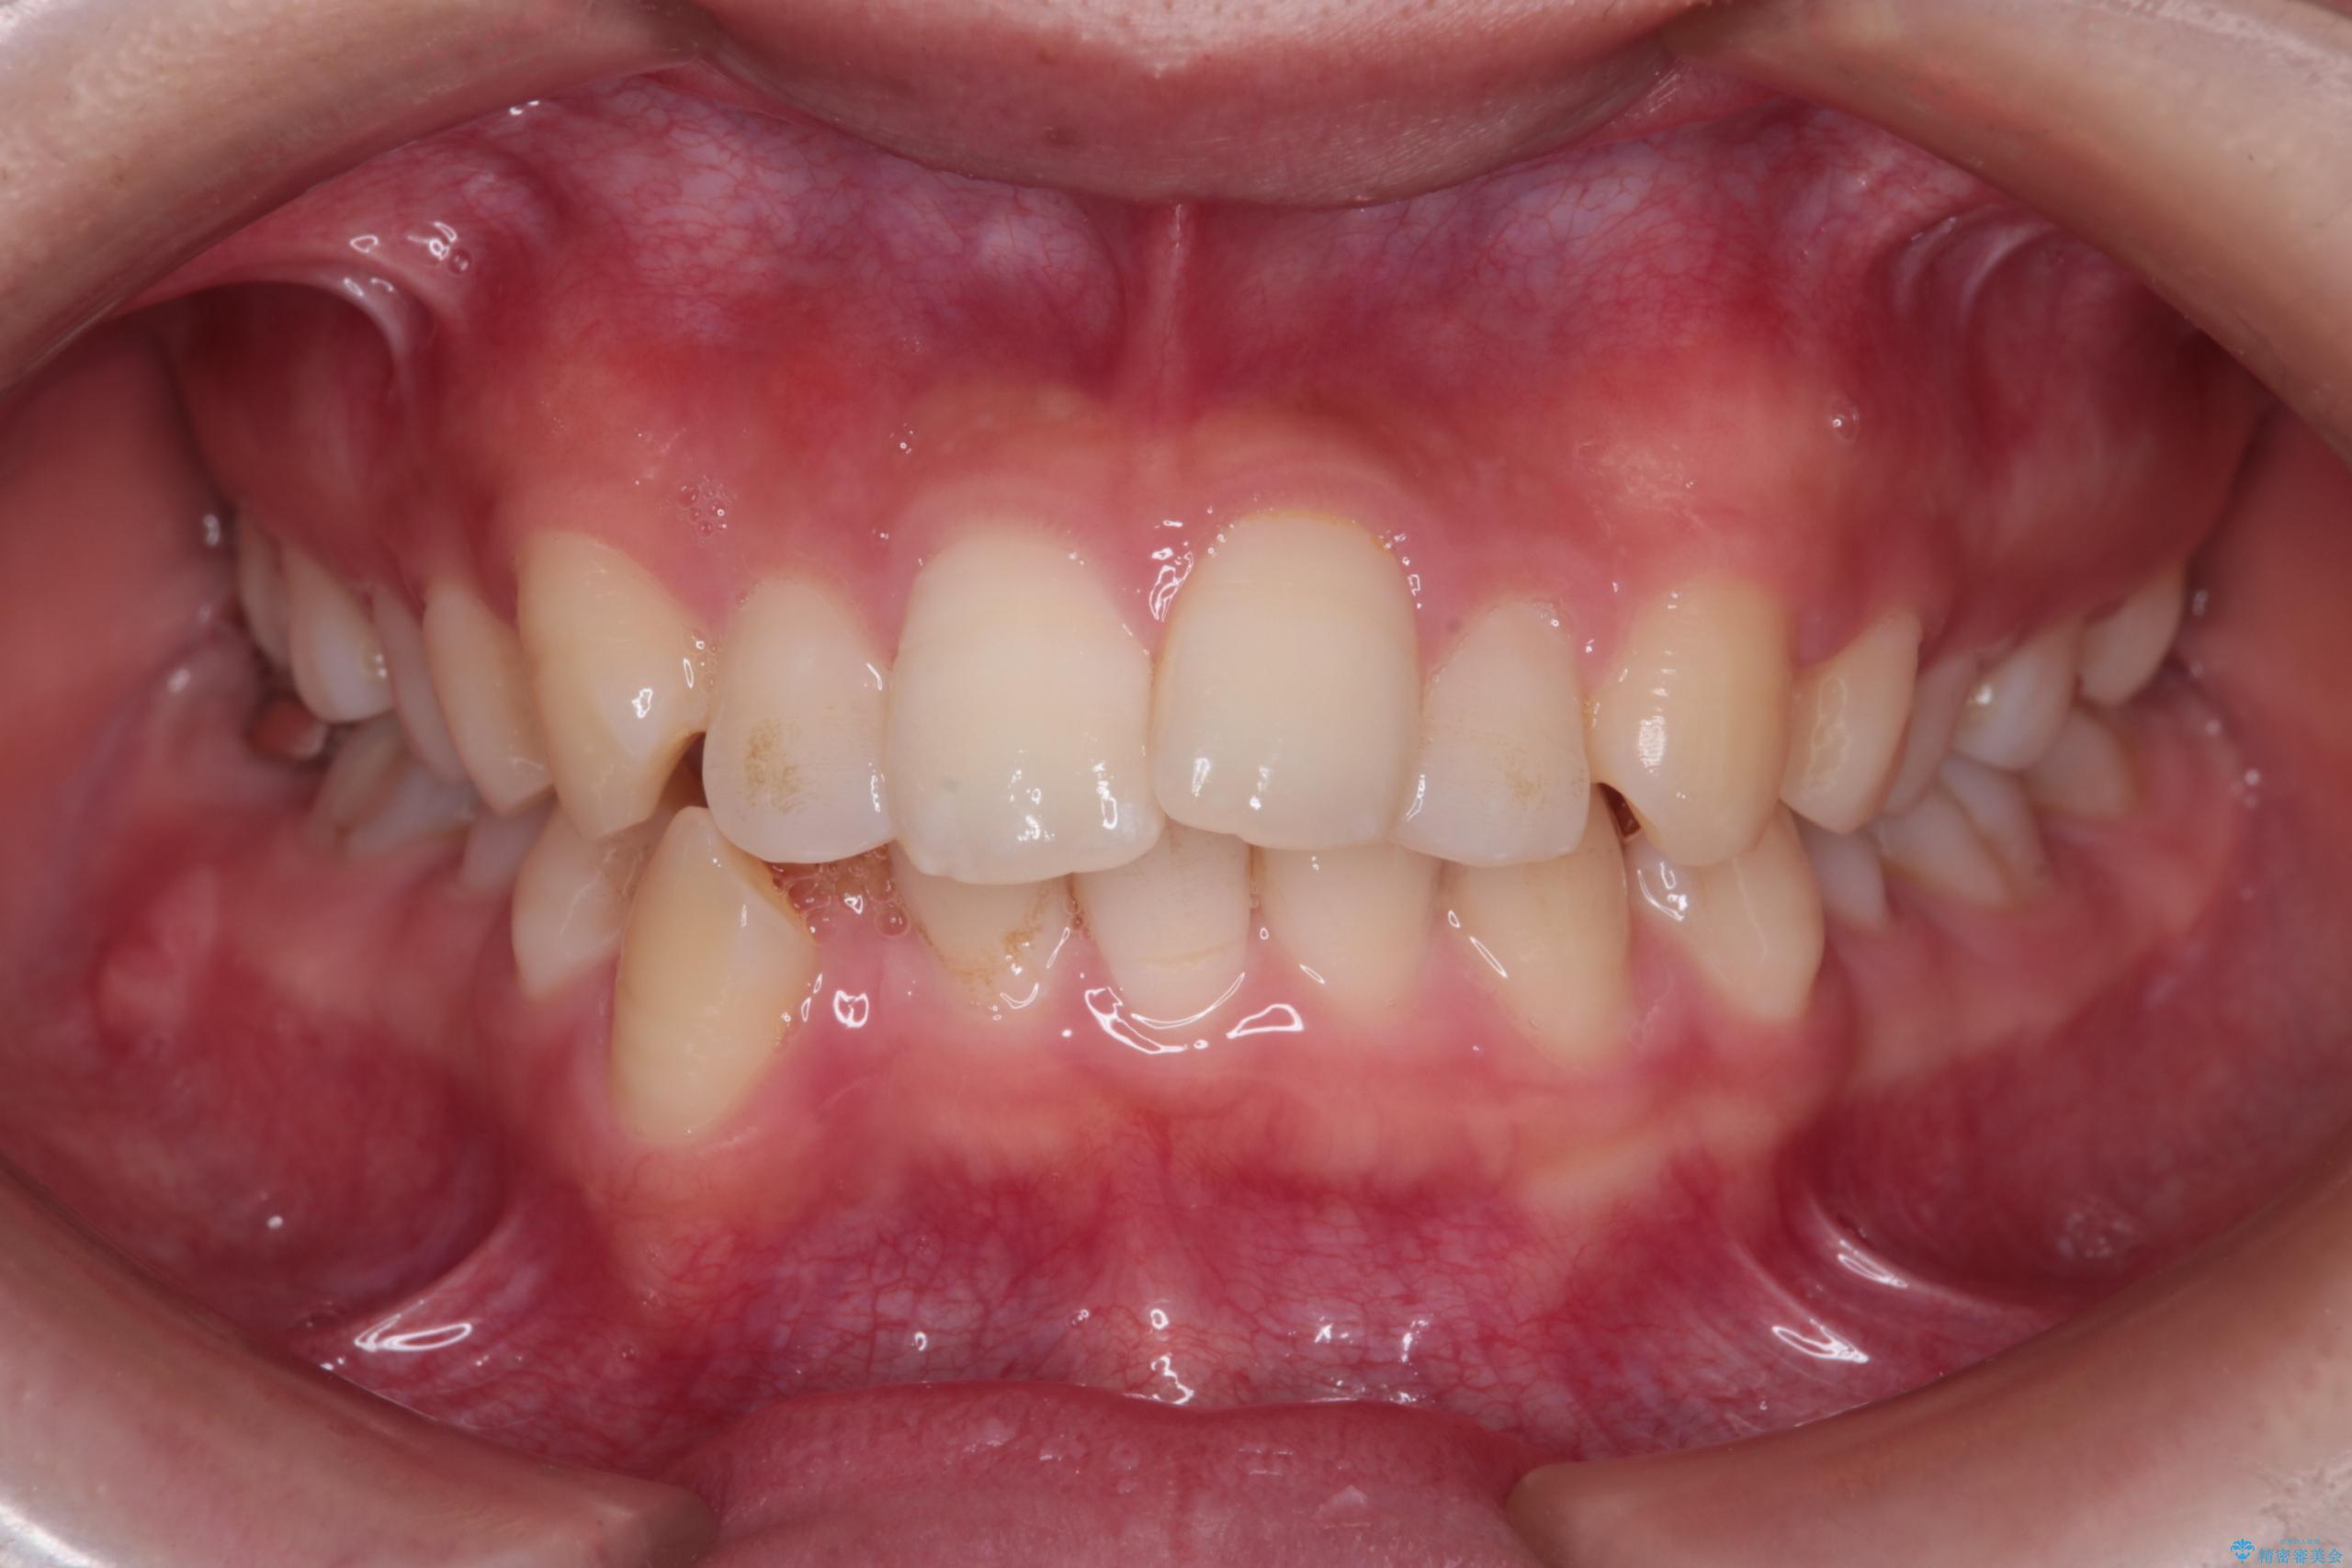

- 前歯から奥歯にかけて歯の重なりが激しい歯のがたつき(重度叢生)を主訴にご来院されました。精密検査の結果、歯が並ぶスペースが大幅に不足しており、歯並びを整え、口元を美しく引っ込めるためには、スペースの確保が必要と診断しました。そこで、上下左右の第一小臼歯(4番目の歯)を計4本抜歯し、そのスペースを利用して歯並び全体を整える抜歯矯正の治療計画を立案。装置には、透明で目立たないインビザラインを採用し、審美性と治療効果の両立を目指しました。

今回の治療では、重度の叢生を改善するため、まず計画通り上下左右4本の小臼歯を抜歯し、歯を並べるための十分なスペースを確保しました。装置には透明で取り外し可能なインビザラインを使用。抜歯によってできたスペースを最大限に活用し、マウスピースを定期的に交換しながら、デコボコを解消しつつ、前歯を効果的に後退させました。

治療の結果、長年の悩みであった重度の歯のがたつきが解消され、口元の突出感も改善。機能的にも安定し、審美的にも美しい、理想的な歯並びを獲得していただけました。